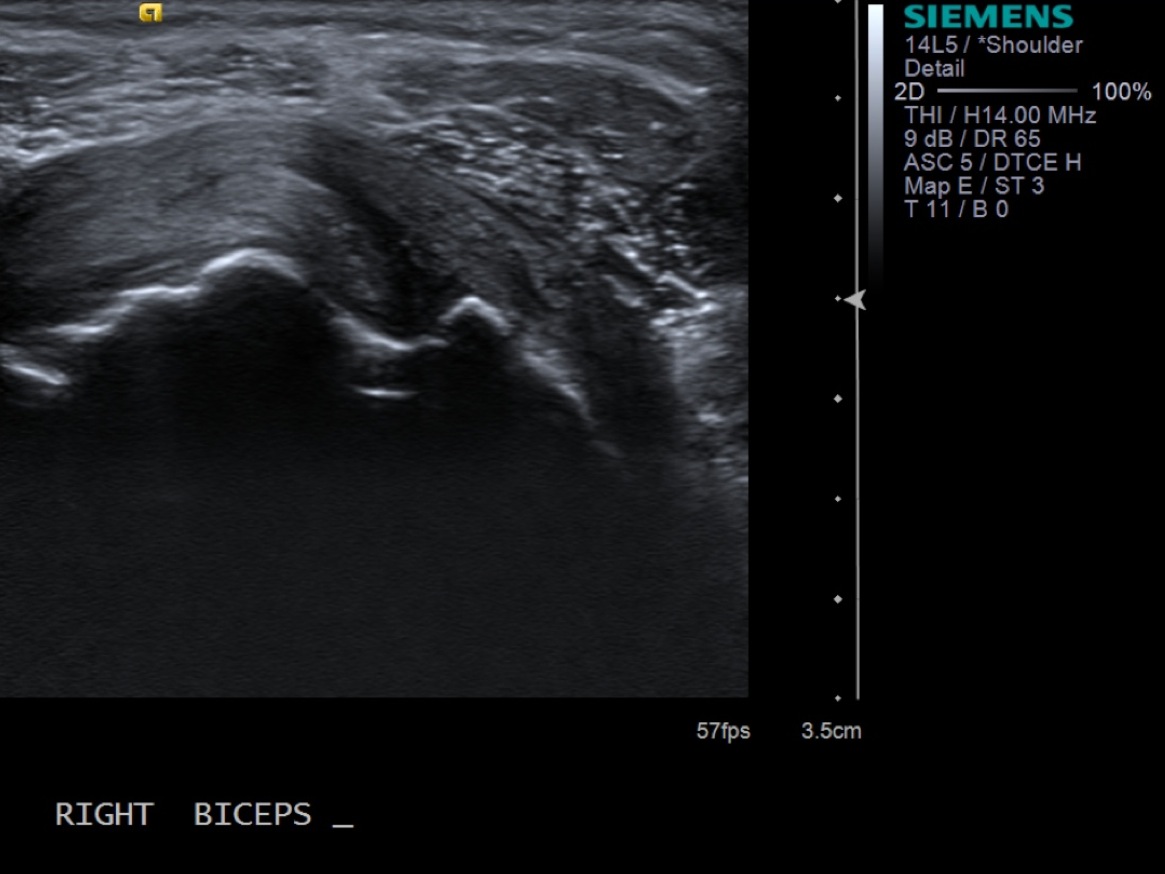

3. Scan patient looking at the biceps tendon (short axis/transverse) extra-articular and at the rotator interval. If there is fluid in the biceps tendon sheath when extra-articular, you can inject at that site. Otherwise, will need to inject at the rotator interval.

• descriptiondescription

Extra-articular biceps tendon in transverse plane